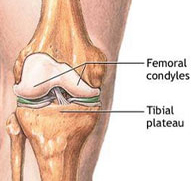

Fracturas del tercio superior de la tibia

Las fracturas en el tercio superior de la tibia suponen el 1% de todas las fracturas y el 8% de las fracturas del anciano. Están causadas por fuerzas violentas que producen desviaciones laterales sobre la rodilla. La osteoporosis en el paciente de edad facilita estas fracturas. Son lesiones que también vemos en el ámbito deportivo fundamentalmente en aquellos deportes que exigen un sobreesfuerzo de la articulación de la rodilla como el esquí, el fútbol o el patinaje. En los deportistas suelen acompañarse, además, de lesiones ligamentosas que pueden pasar desapercibidas si no se realiza una exploración exhaustiva.

El tratamiento de las fracturas del tercio superior de tibia es quirúrgico con la finalidad de devolver a la rodilla su anatomía normal para el rápido inicio de la movilidad articular. Los avances en técnica artroscópica y los nuevos implantes permiten el tratamiento de estas fracturas de una forma poco agresiva y fiable que disminuye las complicaciones postoperatorias y agiliza el tiempo de recuperación.